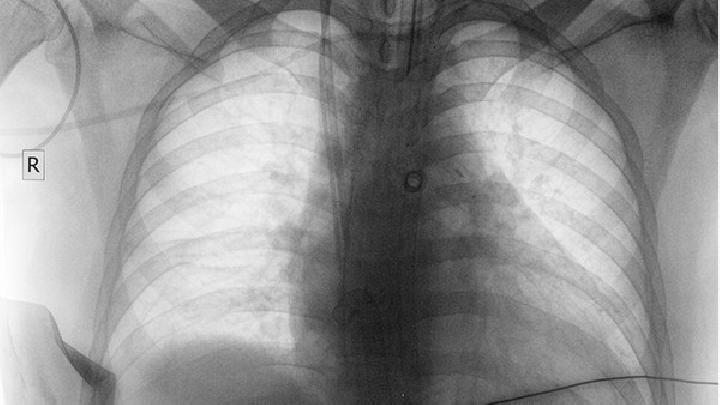

原发性肺动脉高压

原发性肺动脉高压是由什么原因引起的?